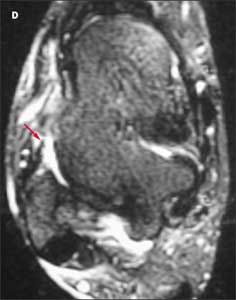

Because the patient’s pain is severe, you order an MRI scan to further evaluate the injury. A T2-weighted axial image reveals disruption of the anterior talofibular ligament (

D,

red arrow).

This patient has a grade 3 injury to the anterior talofibular ligament. In another axial T2-weighted image (E), fluid (yellow arrow) is visible in and around the course of the ligament (red arrow). This confirms that the disruption is acute. The posterior talofibular ligament appears normal and intact (E, orange arrow).

Patients with injuries of this ligament often do not seek medical attention, and it can be difficult to distinguish between acute and more remote injuries on imaging studies. Acute tenderness and fluid at the site of the disruption are 2 clues that can help identify an acute injury.